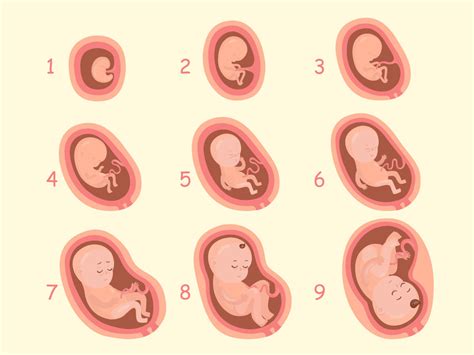

V 31. tednu nosečnosti plod doseže dolžino približno 41 cm in težo okoli 1400 gramov. Ključna sprememba je, da se v tem tednu v kar 75 % primerov obrne z glavico navzdol, kar je idealen položaj za porod. Čeprav se njegova rast nekoliko upočasni, se plod še naprej redi, njegova koža postaja bolj gladka in napeta, lasje pa še naprej rastejo.

Nadaljnji razvoj poteka z neverjetno hitrostjo. V 32. tednu plod doseže težo med 1600 in 1800 grami ter dolžino 42 cm. V tem tednu se priporoča kontrola rasti in kondicije ploda, ki s pomočjo ultrazvoka oceni telesno težo, količino plodovnice, zrelost posteljice ter pretok krvi skozi popkovnične žile. Koža postaja rožnata in gladka, na rokah in nogah pa so prisotni nohti. Če bi se plod rodil v tem tednu, bi njegova možnost preživetja znašala že 95 %.

V 33. tednu plod meri 42 cm in tehta med 1800 in 2000 grami. Kosti so že popolnoma formirane, razen kosti glavice, ki ostanejo nezdružene za lažji prehod skozi porodni kanal. Plod se počasi umirja, saj v maternici ni več veliko prostora za gibanje.

Do 34. tedna plod meri okoli 43 cm in tehta med 2000 in 2300 grami. Njegovo obnašanje je že podobno novorojenčku; posluša, sanja in čuti. Posteljica je zrela, kar pomeni, da bi porod v tem tednu prinesel le majhno možnost resnejših zapletov.

V 35. tednu plod doseže dolžino 44 cm in težo 2500 gramov. Njegova jetra, ledvice in pljuča so popolnoma pripravljeni na življenje izven maternice. Popkovnica je v povprečju dolga 50 cm in prekrita s sluzjo.

Do konca 36. tedna nosečnosti otrok velja za donošenega, z dolžino 46 cm in težo 2700 gramov. Telo je še vedno pokrito s sirastim in mastnim premazom (vernix), ki ščiti kožo. Plod požira vernix in plodovnico, v črevesju pa se nabira mekonij, prvo blato. Če se otrok rodi pred 36. tednom, je nedonošenček, če pa po 42. tednu, je prenošenček.

V 37. tednu plod meri 48 cm, tehta 2950 g in je donošen. Počasi se spušča v medenico, vernixa in lanuga je na koži zelo malo. Intenzivno se razvija imunski sistem. Fantki v tem obdobju rastejo hitreje kot deklice.

V 38. tednu plod doseže dolžino 50 cm in težo 3100 gramov. Dolžina ploda se ne bo več bistveno spreminjala, medtem ko rast težko natančno ocenijo tudi najsodobnejši aparati. Količina plodovnice se zmanjšuje, zato so gibi ploda nežni. Plod večkrat refleksno zagrabi s popkovnico.

Med 39. in 42. tednom nosečnosti porod lahko nastopi kadarkoli. Le 5 % nosečnic rodi točno na rok.